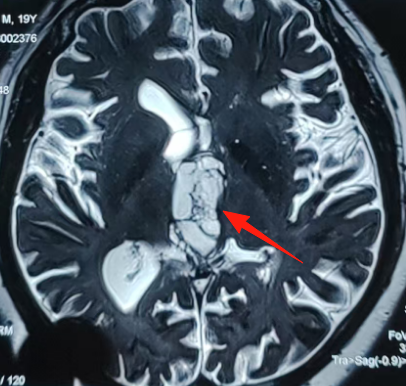

还有一名基底节区海绵状血管瘤患者,因言语不利发现海绵状血管瘤伴内部亚急性期出血可能。高压氧治疗后效果不明显,手术成功率大吗?对于这个问题,巴教授也给出了积极的评估。

分秒必争,只为给疑难神外患者们带来新生的希望。结束患者咨询的巴教授,便健步走向手术室,这里还有一名19岁巨大三脑室肿瘤患者等待着他。愿少年若鲲鹏展翅,越过病痛山峦翱翔万里。